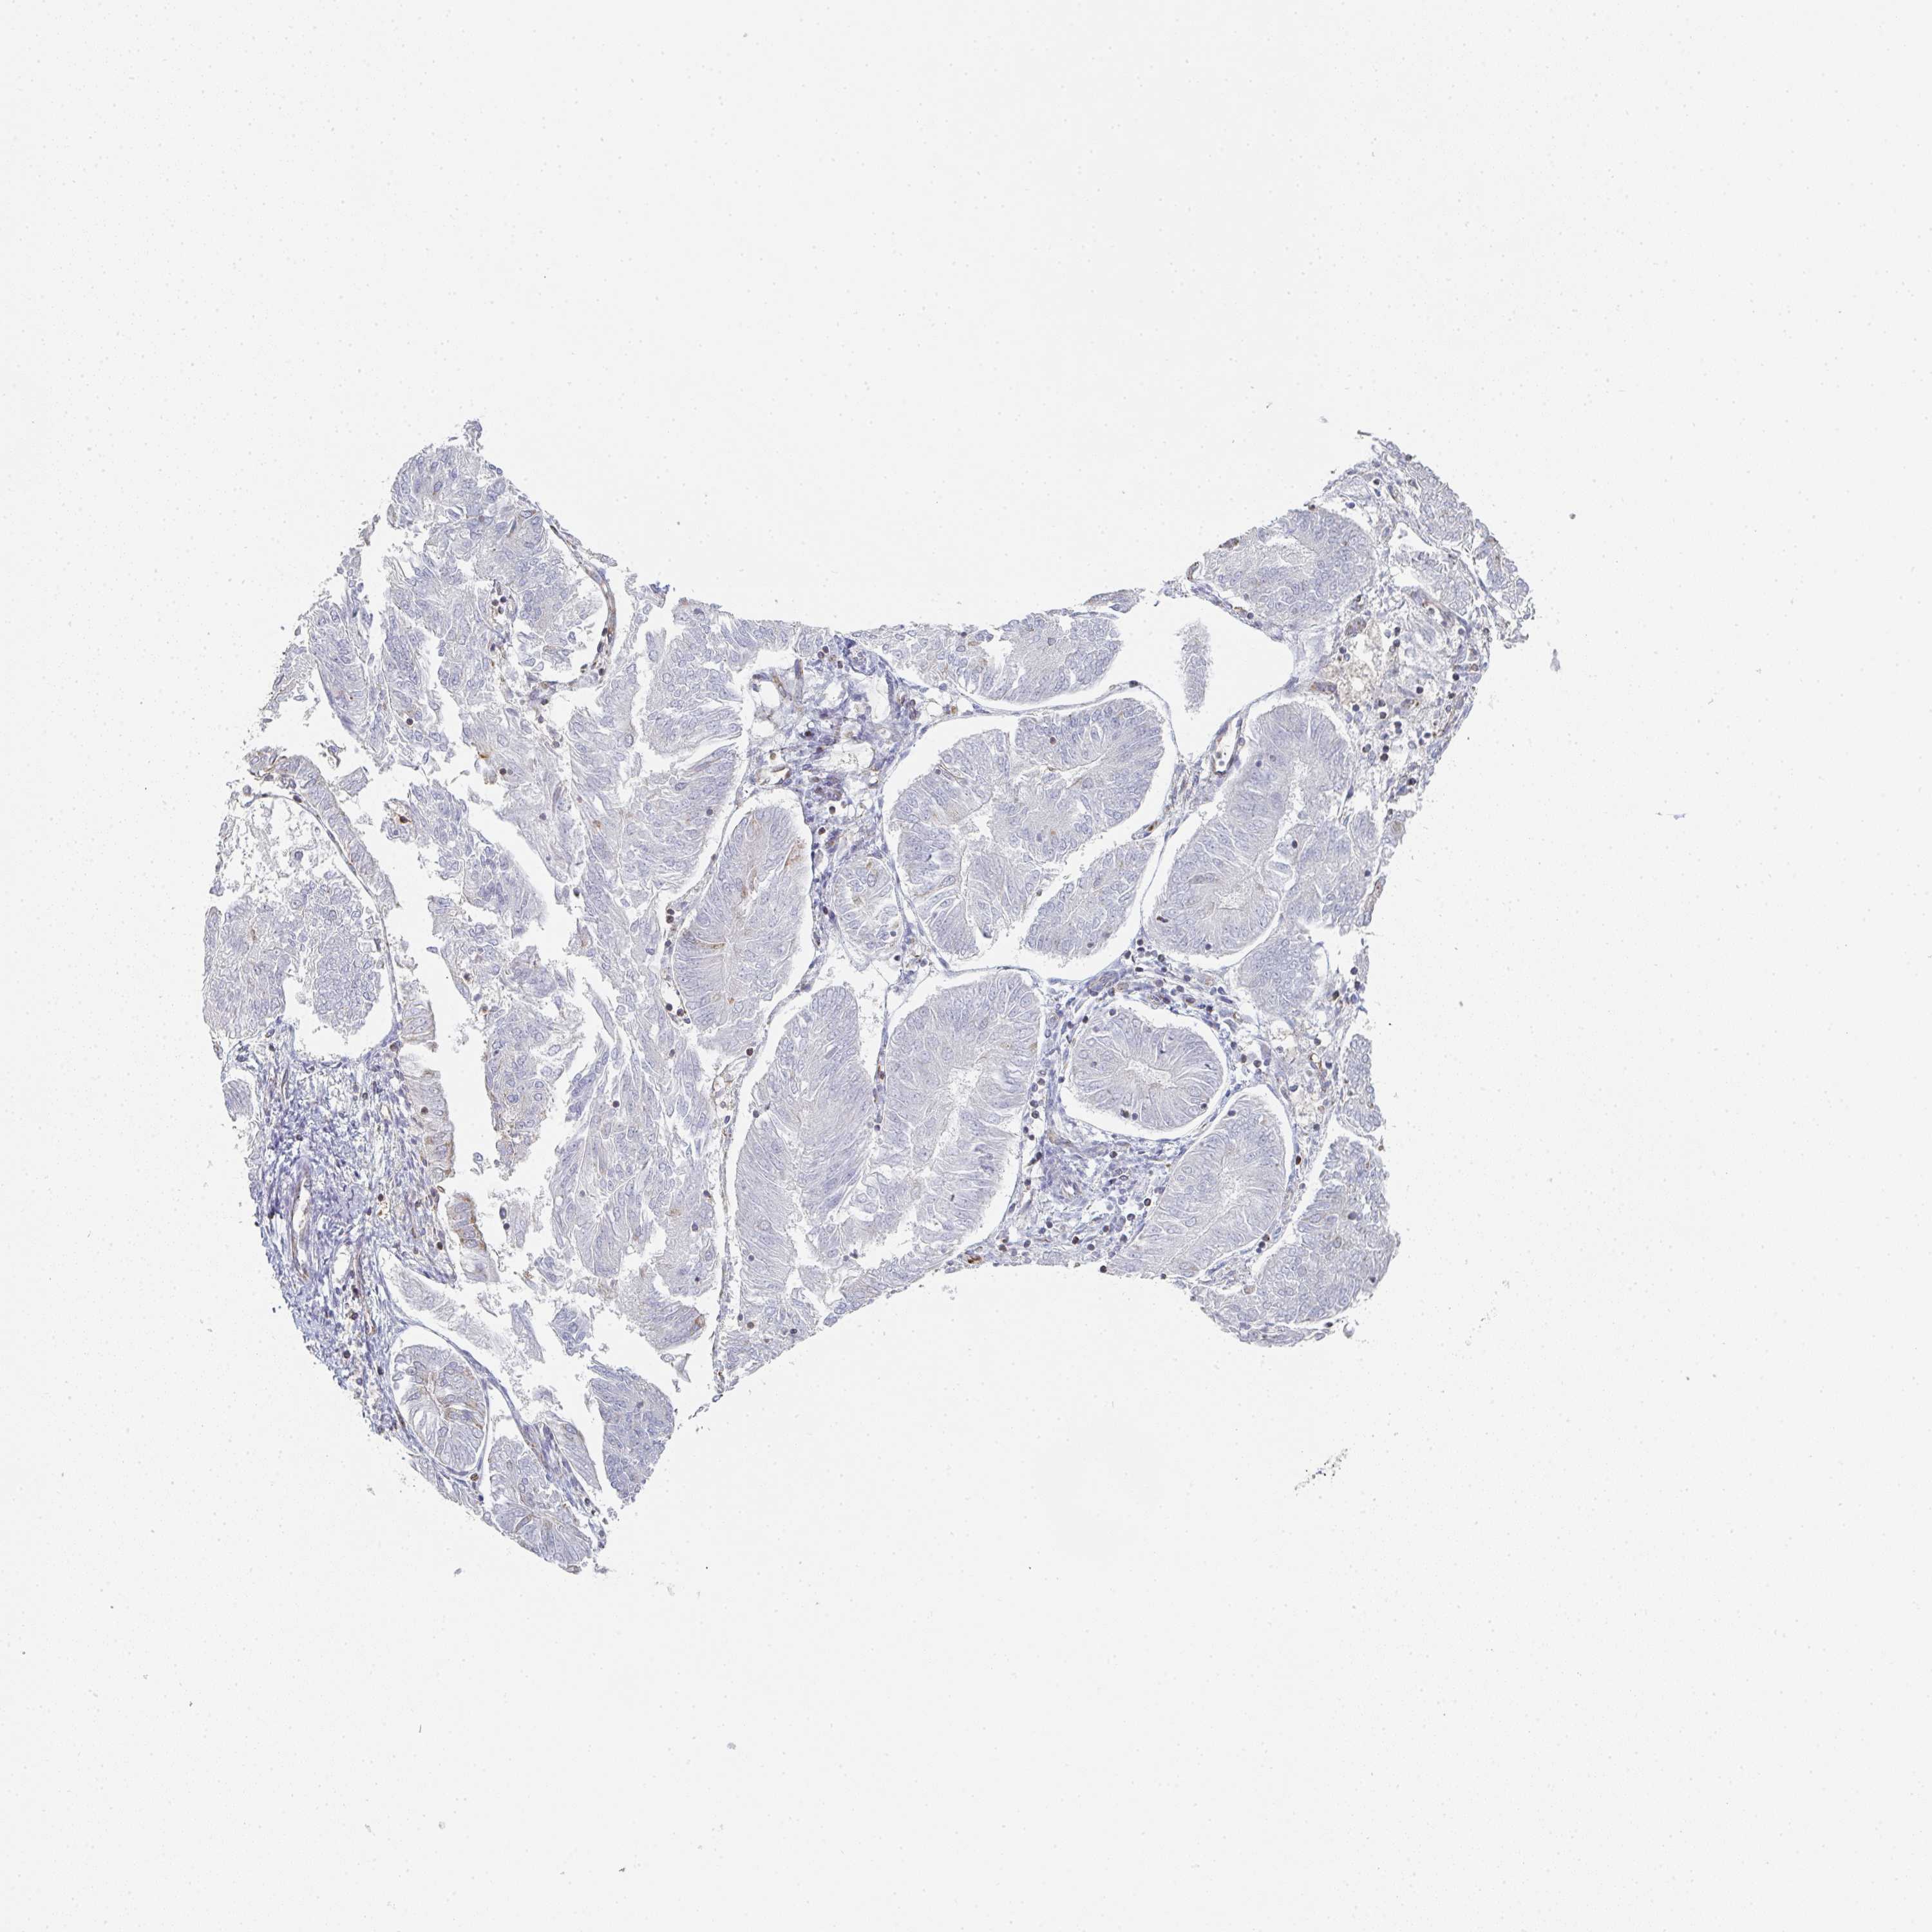

ENDOMETRIAL CANCER - Protein expressioni

A mouse-over function shows sample information and annotation data. Click on an image to view it in a full screen mode. Samples can be filtered based on level of antibody staining by selecting one or several of the following categories: high, medium, low and not detected. The assay and annotation is described here.

Note that samples used for immunohistochemistry by the Human Protein Atlas do not correspond to samples in the TCGA dataset.

Antibody stainingi

Antibody staining in the annotated cell types in the current human tissue is reported as not detected, low, medium, or high, based on conventional immunohistochemistry profiling in selected tissues. This score is based on the combination of the staining intensity and fraction of stained cells.

Each image is clickable and will lead to virtual microscopy that enables deeper exploration of all samples and also displays staining intensity scores, fraction scores and subcellular localization as well as patient and tissue information for each sample.

Antibody HPA023070

Antibody HPA056609

Staining

High

Medium

Low

Not detected

Intensity

Strong

Moderate

Weak

Negative

Quantity

>75%

75%-25%

<25%

None

Location

Nuclear

Cytoplasmic/membranous

Cytoplasmic/membranous,nuclear

Adenocarcinoma, NOS